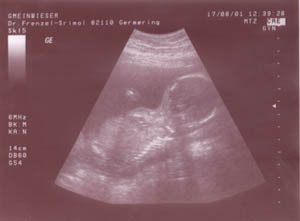

Am 18. August war ich (Anja) bei meiner Frauenärztin und hurra sie hat mir gesagt, dass ich schwanger bin und das schon in der 17. Woche.

Das Bild hier ist von diesem besonderen Tag.